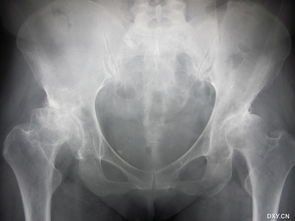

做了人工關(guān)節(jié)置換手術(shù)之后,患者需要在今后漫長的生活中注意多加保護(hù),注意護(hù)理,這樣才能保證人工關(guān)節(jié)的使用壽命。

人工關(guān)節(jié)置換術(shù) 后的注意事項(xiàng) 1、減輕體重: 髖、膝關(guān)節(jié)承受的力量大部分是人體的重力,所以減輕體重就能減少對關(guān)節(jié)的壓力。術(shù)后要合理安排飲食,保持體重控制在正常范圍內(nèi),以減輕對關(guān)節(jié)的磨損。

2. 每年拍攝一次膝關(guān)節(jié)正側(cè)位片(X光)

了解假體有無發(fā)生移位,了解有無發(fā)生假體周圍骨吸收。